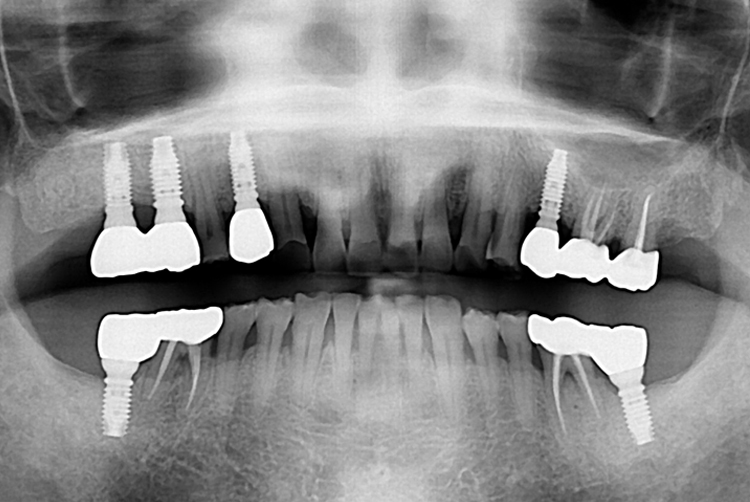

[임플란트] 임플란트

치료후 : 2019-05-08

세종치과는 많은 환자와 다양한 케이스를 바탕으로 항상 편안한 임플란트 수술을 제공하고자 노력하고,

오래동안 튼튼히 쓸 수 있는 임플란트 수술을 가장 큰 목표로 삼고 있습니다